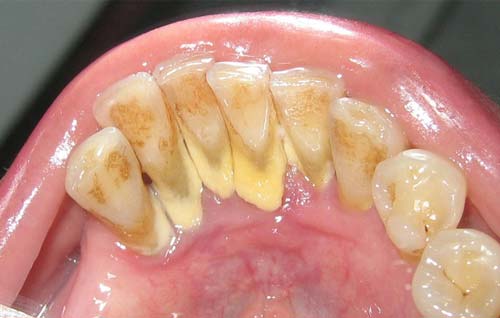

جرم که معمولا به عنوان رسوب (tartar) از آن یاد میشود، به پلاکهای سخت شده گفته میشود. در تصویر زیر مشاهده میکنید که جرم شبیه به یک لایه ضخیم خامه ای به دندان (در مرز دندان – لثه) چسبیده است.

“رنگ آن معمولا سفید یا زرد مایل به سفید است و سختی آن مشابه گل بوده و به راحتی از سطح دندان جدا میشود. پس از زدودن جرم، ممکن است خیلی زود دوباره جرم تشکیل شود به خصوص در سطح زبانی (پشتی) دندانهای پیشین ماندیبولار. رنگ جرم تحت تاثیر تماس با مواد مختلف مانند تنباکو و رنگهای غذایی ممکن است تغییر کند. ”

جرم در هر گونه سطح دندانی و حتی زیر خط لثه تشکیل میشود. یکی از سطوحی که جرم به راحتی در آن پنهان میشود سطح پشتی دندانهای جلویی فک پایین است. غدد بزاق زیر زبان، کلسیم زیادی منتشر میکنند که به پلاکها کمک میکند سریعتر سخت شوند.